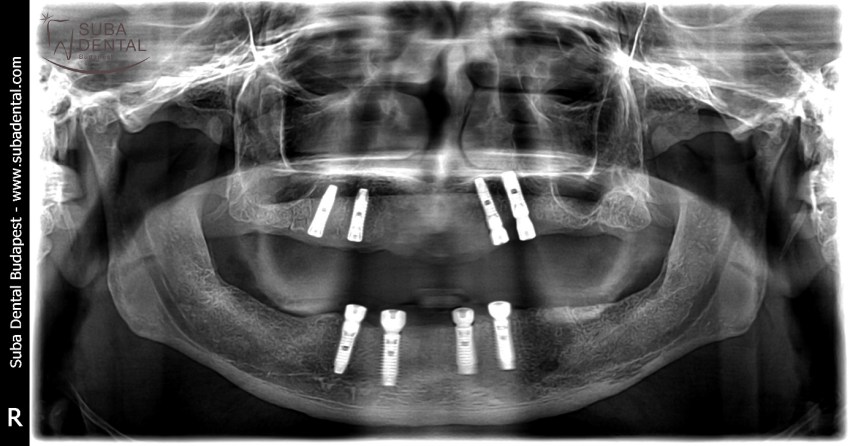

Panoramic radiograph of chronic dental foci, teeth affected by periodontal disease, and root remains. All teeth had to be extracted

Follow-up panoramic radiograph following the installation of implants. Our patient would have needed a bone graft but was completely inconvincible. Therefore, a total of 4 implants were installed per jawbone that would support a bar denture. The dental foci and infections totally destroyed bone width and bone height as a result of which the mounting of implants required great effort and could only be carried out in an asymmetric fashion.